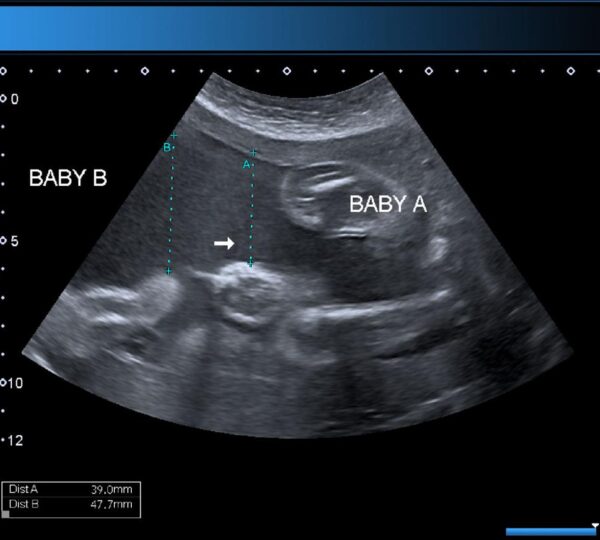

Medical research shows that twin pregnancies naturally carry higher risks compared to single pregnancies. These risks include premature birth, low birth weight, gestational diabetes, and pregnancy-related hypertension.

Because of these factors, twin pregnancies are classified as higher-risk pregnancies and require more frequent prenatal monitoring to ensure the health of both the mother and babies.

In later-life pregnancies, medical supervision becomes even more important. Healthcare providers typically schedule regular ultrasounds, blood tests, and physical evaluations to closely monitor fetal development and maternal health.